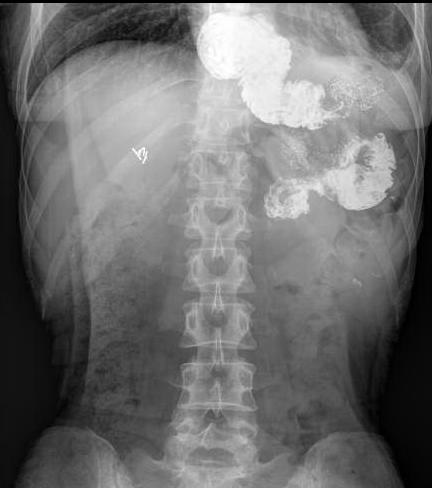

44 女性 胃癌,食管空肠RY吻合,放化疗。拒绝鼻饲管,持续性体重降低和消瘦。

吞钡,没有机械性梗阻,但钡剂明显滞留

钡剂滞留